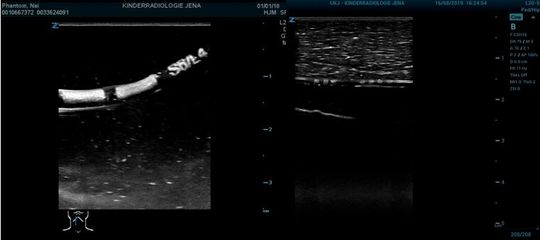

Die kugelförmigen Gaseinschlüsse im markierten Bereich bewirken eine stärkere Reflexion der Schallwellen, so dass diese im Ultraschallbild (B-Modus) auch bei ungünstiger Schräglage der Vorrichtung deutlich heller gegenüber den umgebenden Substanzen abgebildet werden (s. Abb. 3). Die Markierungen können mit hoher geometrischer Variabilität hergestellt werden, selbst filigrane Schriften sind möglich und können im Ultraschallbild gelesen werden.

Abb. 3: Markierte Katheter im Ultraschallbild: Testmodell Wasser (l.) und Schweineleber (r.).

(Bild: TITK)

Für die Untersuchungen der Ultraschallsichtbarkeit wurden verschiedene Vorrichtungen in einer 45°-Lage zur Schallrichtung in einer Tiefe von 2 bis 4 cm sowohl in einem Wasserbad als auch in einem Ultraschallphantom mit körpergewebeähnlichen Eigenschaften und in einer Schweineleber positioniert. Die im konventionellen B-Mode aufgenommenen Ultraschallbilder einer 0,7 mm dünnen Nadel bei einer Ultraschallfrequenz von 8 MHz zeigen, dass die Markierungen deutlich heller mit guter Konturenschärfe gegenüber den umgebenden Substanzen abgebildet werden.

Abb. 6: Ultraschallbilder markierter Kanülen: Gewebemodell Wasser (l.), Testphantom für Ultraschall (Mitte) und Gewebemodell Schweineleber (r.).